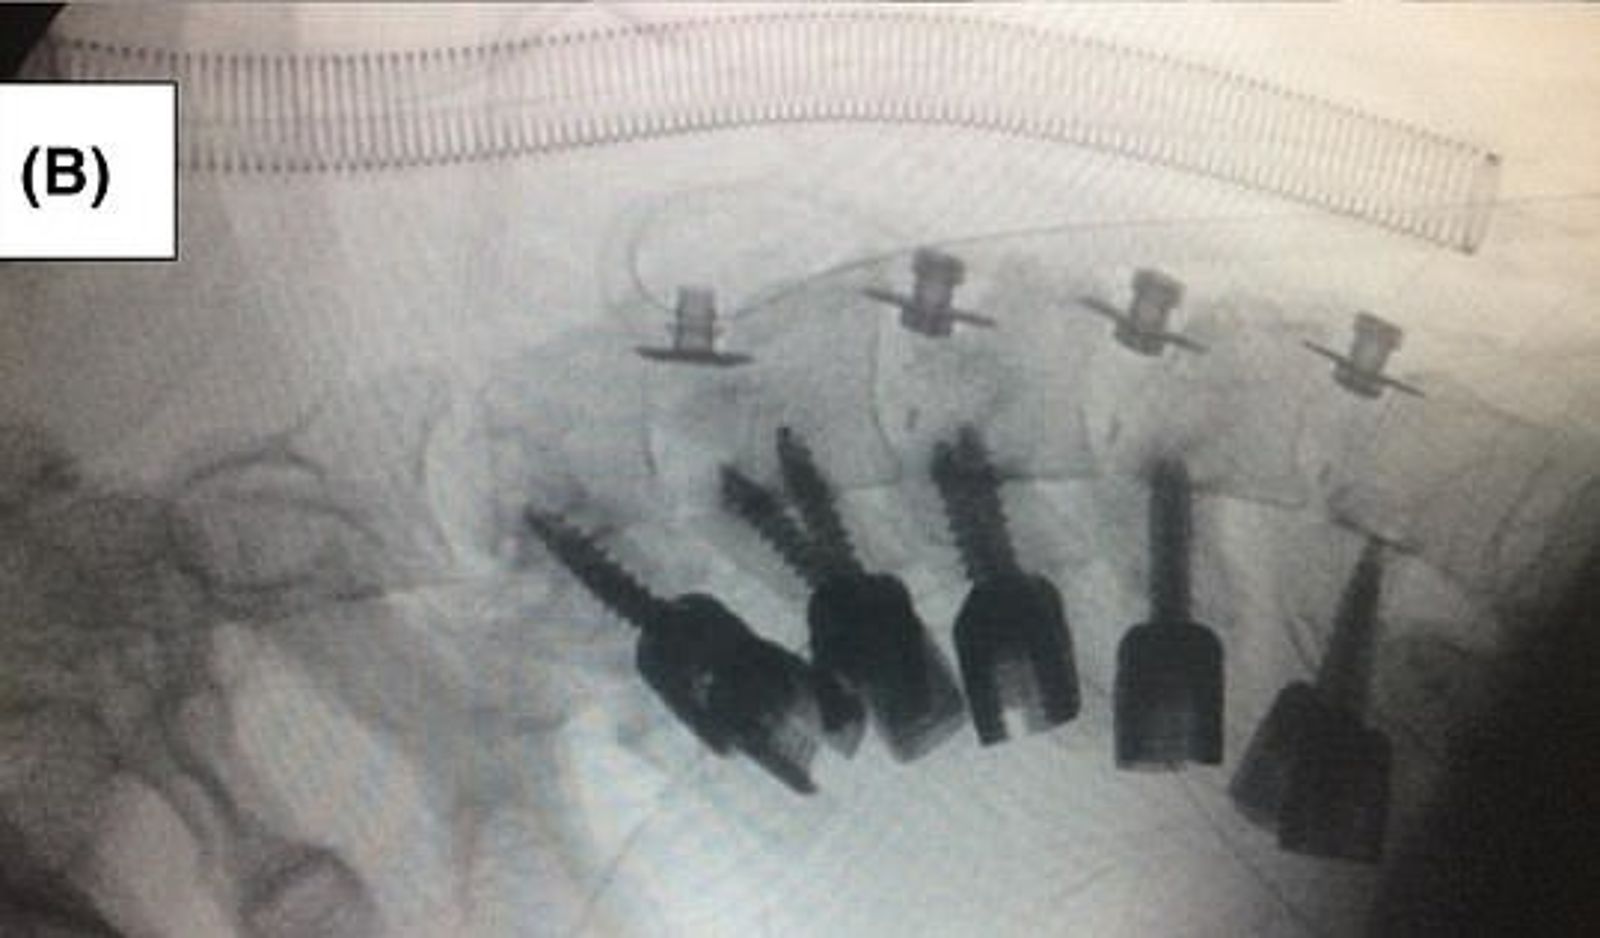

醫師表示,男子出現頭顱下垂的症狀,至少持續15個月,而且醫師也研判,這已經無法用物理復健的方式來矯正,必須動手術開刀。報導指出,醫師去除男子變形的頸部骨骼,並用宛如螺絲起子的醫療器具,把剩下的頸椎骨骼固定住,之後男子再戴了3個月頸部固定器。

醫師說,男子術後恢復良好,顯示這次脊椎矯正手術是成功的。不僅如此,男子也同時戒毒成功。